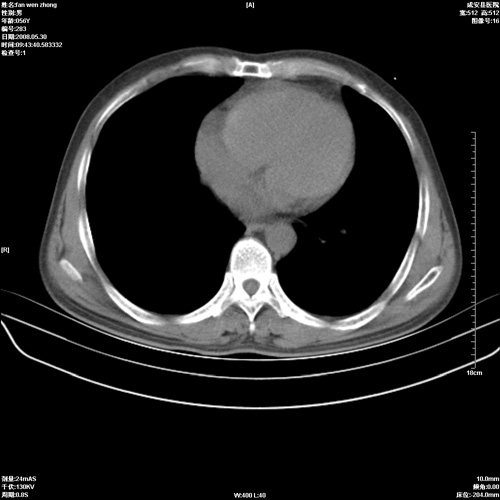

病人 男 56岁 一周前高热,体温达39-40度,经抗炎治疗后,体温渐降,达37,5-38度,轻微咳嗽,胸部不适 查白细胞为1.3万 行ct检查,请分析。

双肺内可见多发结节状病灶,并见小空洞,病人高热,白血球增高,应该是典型的迁徙性肺脓肿(多为金黄色葡萄球菌感染)。查一下口腔等其它部位有无感染灶。

双肺内可见多发结节状病灶,并见小空洞,病人高热,白血球增高,应该是典型的迁徙性肺脓肿(多为金黄色葡萄球菌感染)。建议治疗后复查.